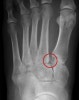

양측 체중부하 상태, 체중부하하지 않은 상태에서 족부 정면 X-ray 사진을 찍습니다.

제 1, 2 중족골 기저부의 간격이 건측에 비해 크고 체중부하 상태에서의 해당 간극의 변화가 건측에 비해 큽니다.

내측, 중간 설상골 사이가 벌어져 있으며, 설상골간인대도 파열되어 있습니다.

X-ray : Lisfranc 인대 손상 (Lisfranc injury, Midfoot sprain)